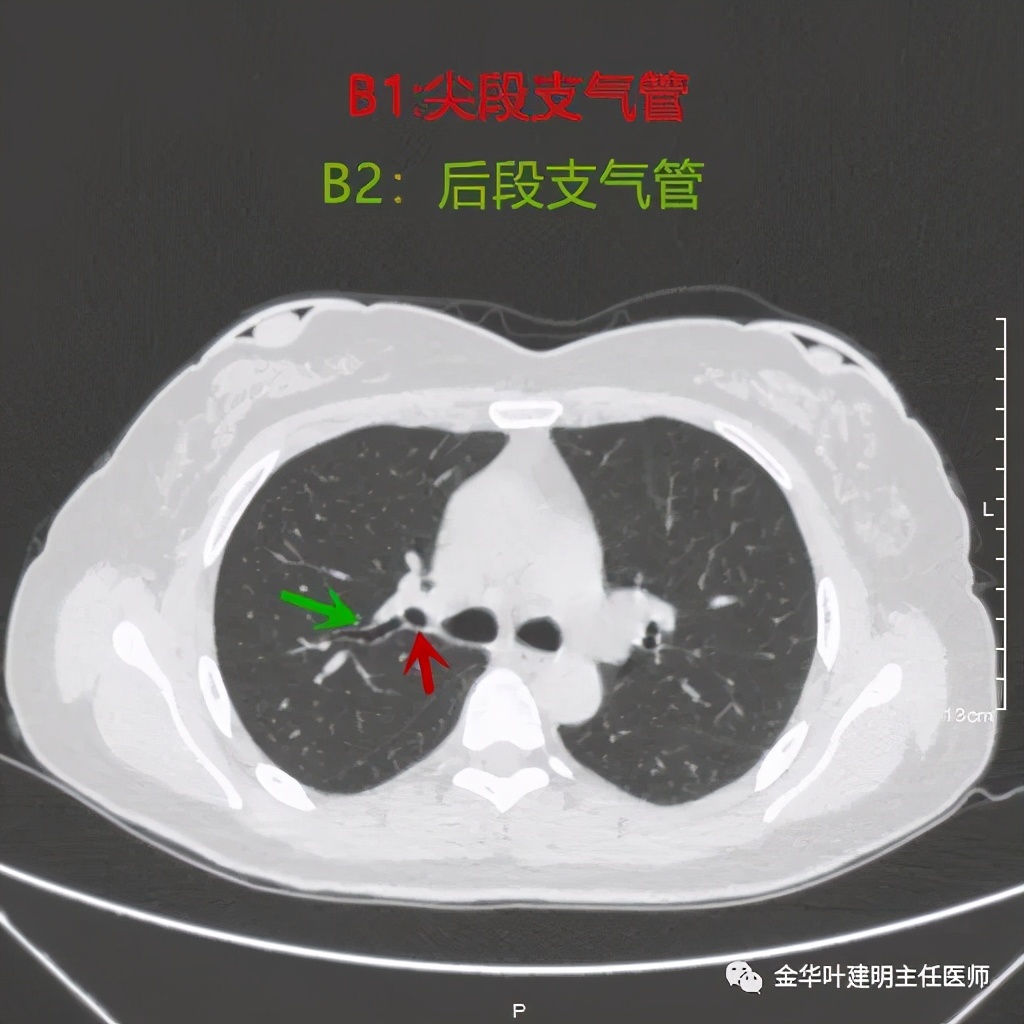

尖段:因动图只能插入一次,所以尖段与后段的动图无法展示,我们选取最佳层面进行标注相关的亚段支气管:

因为横断面的关系,红色箭头示尖段支气管的开口,绿色箭头示后段支气管